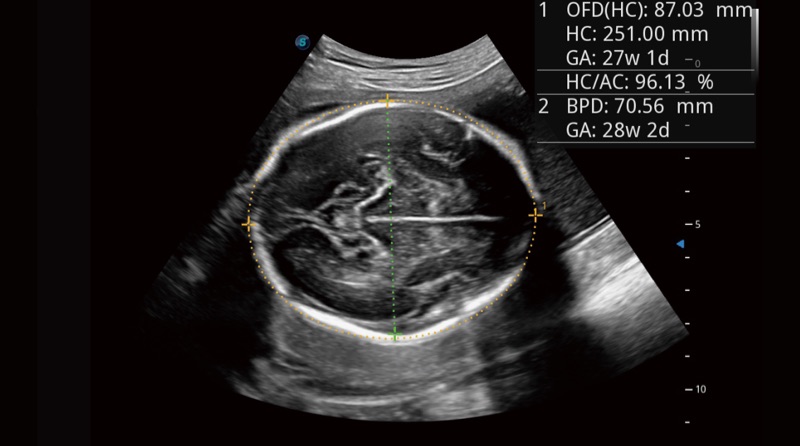

Basierend auf einem verlässlichen Deep-Learning-Algorithmus für Big Data ist S-Fetus eine brillante Komplettlösung für automatische Standard-Ebenen-Erfassung und Messung. Mit nur einem Klick werden gängige fetale Biometrie-Ergebnisse mit hoher Intelligenz, Genauigkeit und Effizienz erzielt, um einen beispiellosen Bedienungskomfort zu gewährleisten.

Dank der Unterstützung von Auto OB wird eine schnelle und hoch effiziente fetale Biometrie erreicht. Gleichzeitig kann diese auf Deep Learning basierende Methode zu konsistenteren Ergebnissen führen und die Variabilität, die vom Anwender abhängig ist, effektiv reduzieren.